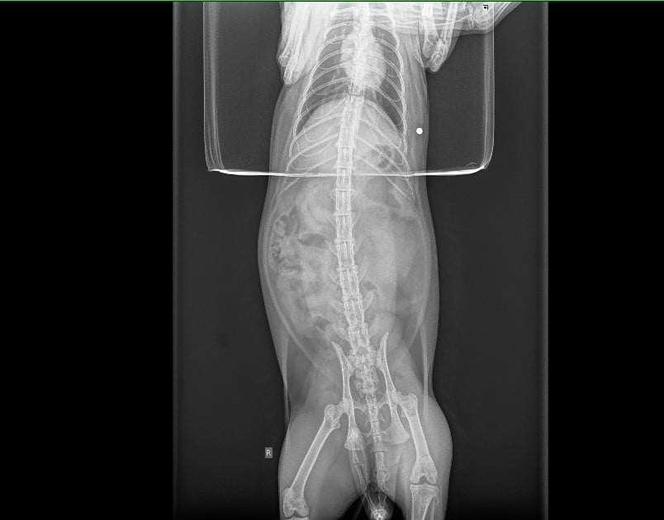

Właścicielka z kotem natychmiast pojechała do weterynarza. Smutną prawdę u weterynarza wykazało prześwietlenie RTG. Okazała się, że kotek został postrzelony śrutem z wiatrówki. Sadysta trafił w go w brzuszek.

Śrut utkwił w jamie brzusznej, ale na szczęście z boku. – Śrut mógł przecież uszkodzić jakiś organ i kot padłby. Nie rozumiem komu przeszkadzają koty – pisze nasza czytelniczka.

W styczniu 2021 r. doszło do podobnej sytuacji. Wtedy także ktoś postrzelił kota naszej czytelniczki. Cynamon został trafiony w okolice kręgosłupa. Na zdjęciu RTG było widać śrut przy kręgosłupie zwierzaka. Nikogo wtedy nie zatrzymano.